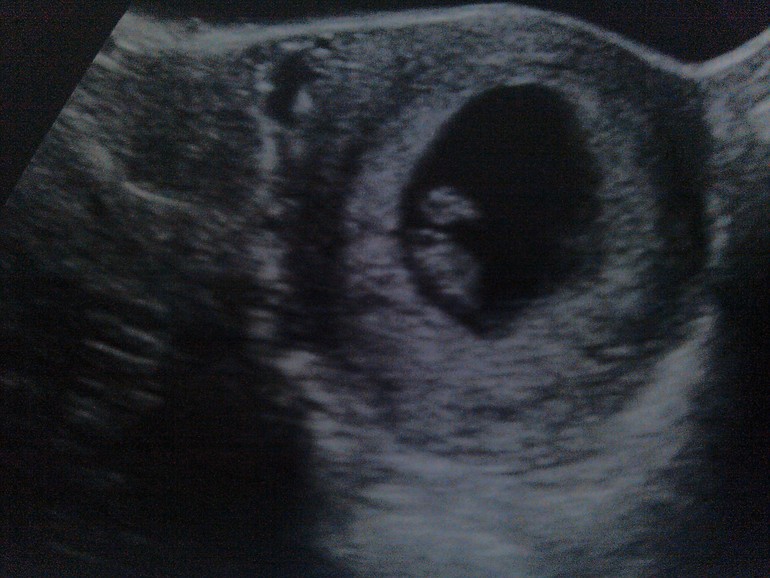

С нетерпением жду очередного УЗИ, 12 недель для меня срок, связанный с грустными воспоминаниями, как и 8 недель. Понимаю, что волноваться не надо, что сама себя опять накручиваю, но чем ближе дата УЗИ тем чаще пробивает холодный пот.